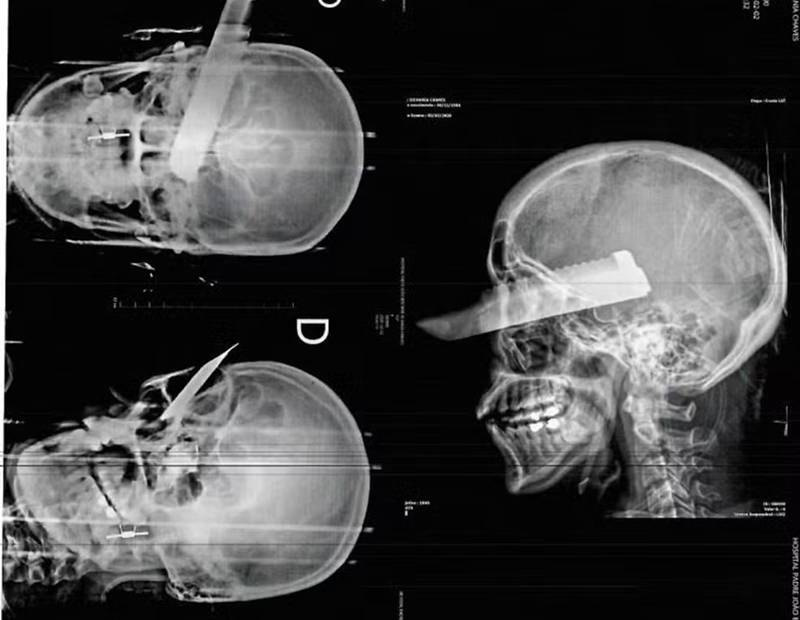

Com hematomas severos no rosto, braços e pernas, além de uma lesão grave no olho direito, ela foi socorrida pelo Corpo de Bombeiros e transferida para o Hospital Regional do Oeste, em Chapecó.